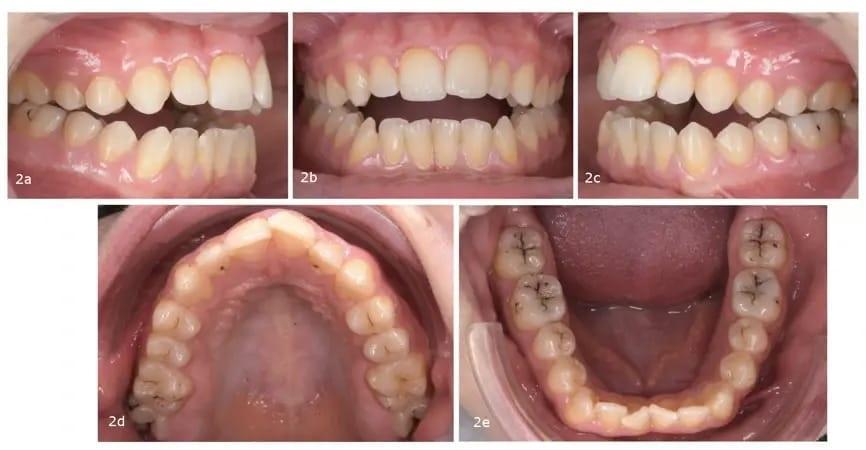

Клинический осмотр выявил передний открытый прикус, по классификации III класса, сужение верхней челюсти, легкая скученность в обеих челюстных дугах и отклонение средней линии нижней челюсти вправо. Верхняя челюсть имела треугольную форму, в то время как нижняя челюсть была квадратной по форме (фото 2).